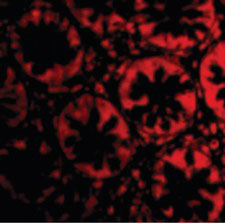

Images |

Immunofluorescence of TEM2 in Human Colon cells with TEM2 antibody at 20 ug/ml.